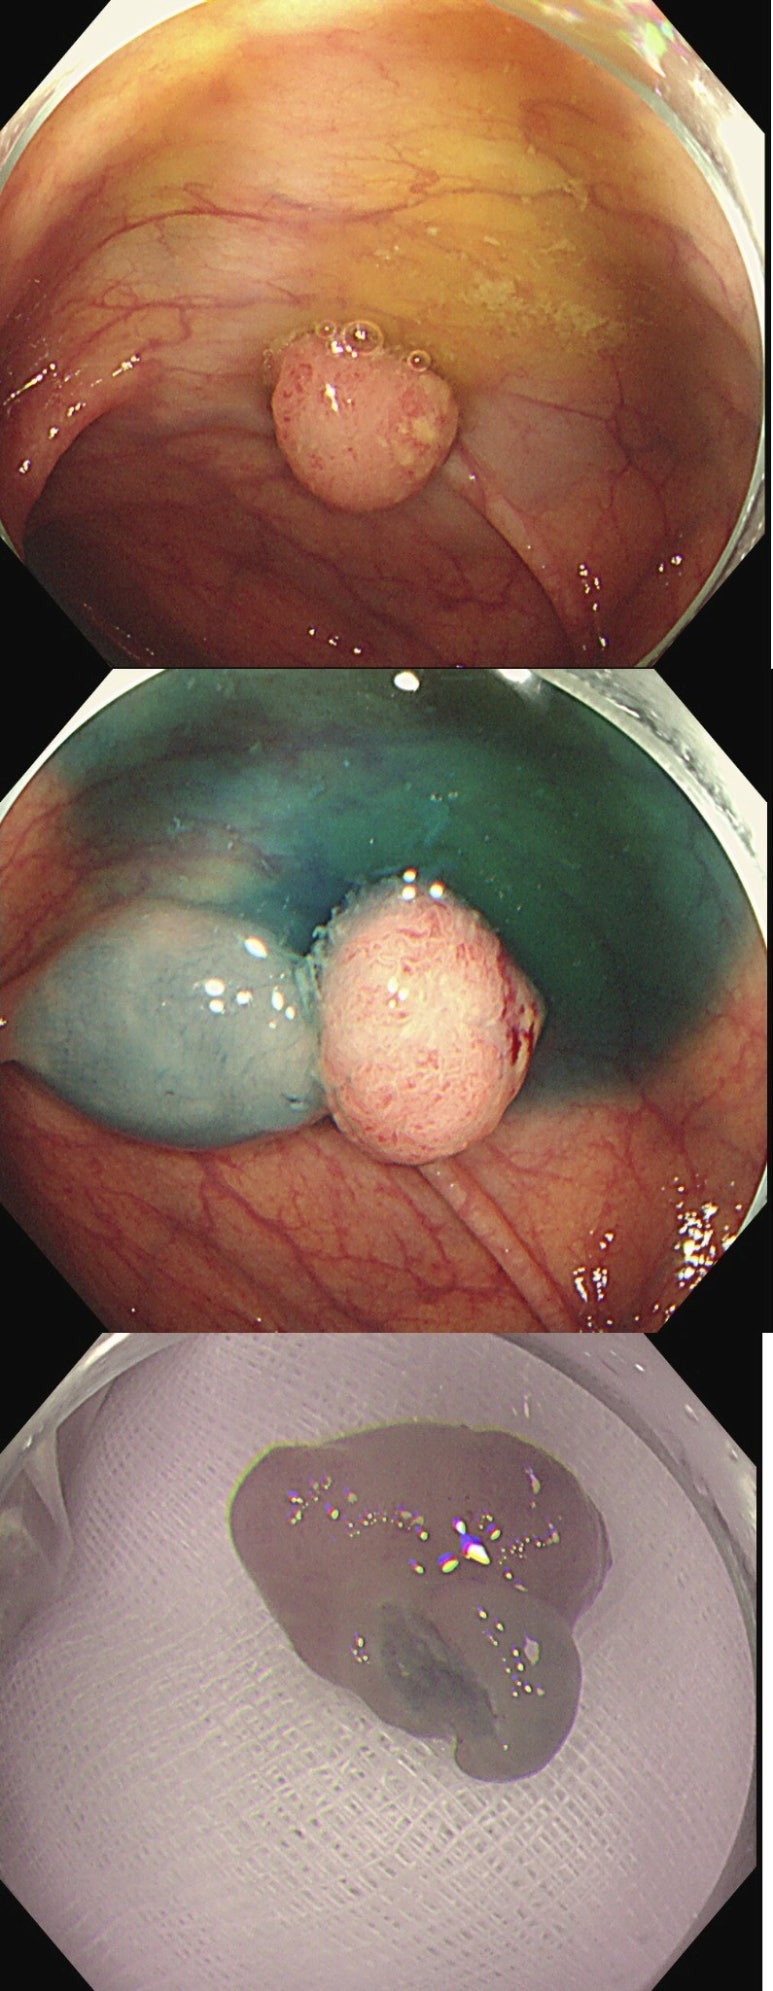

60세 여성 환자에서 시행된 대장 내시경 중,

비교적 평범한 용종으로 보이는 병변을 제거하였습니다.

그러나 조직검사 결과는 놀랍게도

'중등도 분화 선암(Adenocarcinoma, moderately differentiated)'으로 확인되었고,

점막하(submucosal) 침윤까지 동반된 상태였습니다.

육안 소견상 악성이 의심되지 않았기에 더욱 뜻밖의 결과였지만,

절제연이 명확하고 침윤 깊이가 1,000μm 이내로 확인되어

상급병원 병리 슬라이드 리뷰 후에도 추가 치료 없이 경과 관찰하기로 결정되었습니다.

아래는 실제 증례의 내시경 사진입니다.